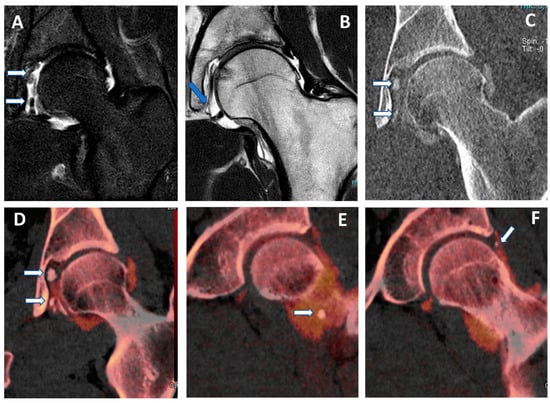

Figure 5.

Capsular, labral, and loose calcifications in femoro-acetabular impingement. On MRA coronal STIR and T1 weighted images (A,B), it is possible to recognize subtle filling defects (arrows on (A)) and capsular thickening (blue arrow in (B)). On the DECTA VMI 1 mm coronal reconstructed image (C), calcifications are partially and erroneously subtracted (arrows). The corresponding DECTA iodine map images (D–F), reconstructed on the coronal plane (1 mm thickness), clearly show the presence of loose bodies and capsular and labral calcifications (arrows).